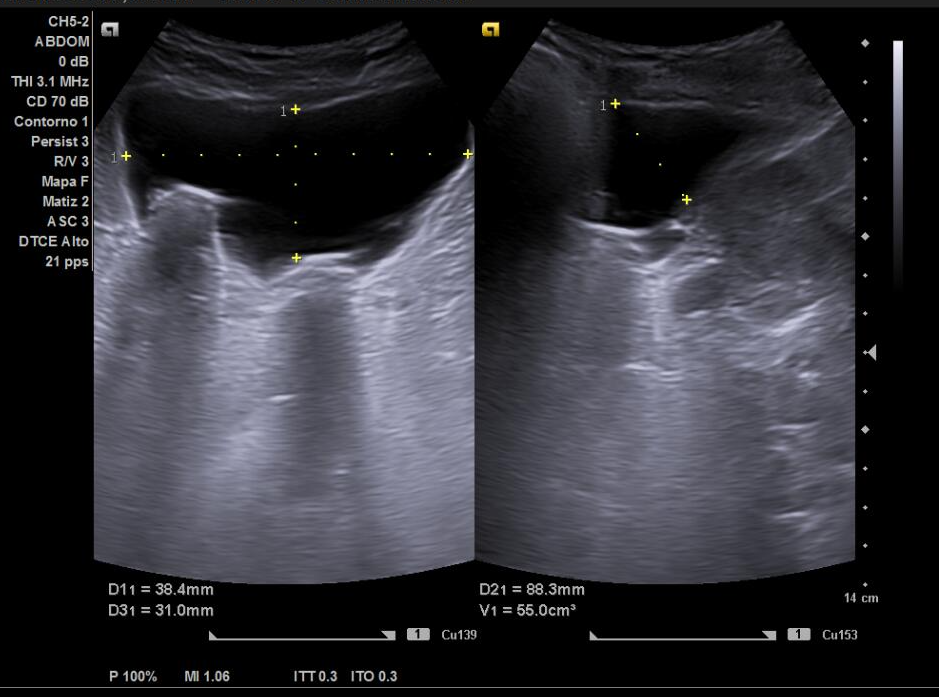

Estuvo en seguimiento por Urología con motivo de litiasis renales izquierdas no obstructivas que se trataron con litotricia extracorpórea e hidronefrosis derecha grado 2-3 secundaria a litiasis ureteral derecha y litiasis vesicales. Además, en esa última visita hace un año se diagnosticó de Hiperplasia benigna de próstata (con volumen prostático de 78 cc) pautando Urología Dutasterida, Tamsulosina y Serenoa repens, descartando otras patologías nefrourológicas.

Acude a consulta de primaria por presentar aumento de urgencia miccional y nicturia habitual desde hace unos meses pese a tratamiento indicado por parte de Urología. Presentando asimismo microhematuria en anormales y sedimentos de orina.

Por este motivo se solicita ecografía clínica para valorar la vía urinaria.

Ecografía clínica urinaria:

Diagnóstico: ureterectasia con ureteroceles bilaterales.